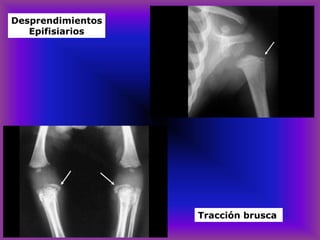

Desprendimientos

Epifisiarios

Hipercaptación

ósea en la

gamagrafía

Fractura por desprendimientos Tracción brusca

Tracción brusca